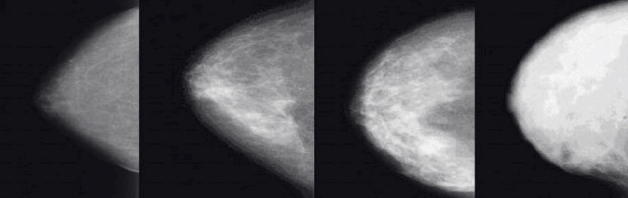

치밀유방은 유방 내 지방조직보다 유선조직과 결합조직의 비율이 높아 유방의 밀도가 높은 상태를 말합니다. 쉽게 말해 유방 내부에 실질 조직(유선과 결합조직)이 많고 지방 조직이 적은 상태입니다. 유방 밀도는 유방촬영술(맘모그래피)을 통해 확인할 수 있으며, 일반적으로 4단계로 분류됩니다.

둘째, 치밀유방은 유방촬영술에서 유방 조직과 종양이 모두 하얗게 보여 암을 발견하기 어렵게 만듭니다. 이로 인해 조기 발견이 지연되어 예후가 나빠질 수 있습니다. 특히 고도 치밀유방(유방 밀도 75% 이상)의 경우 유방암 진단 확률이 크게 증가하므로 정기적인 검진과 조기진단이 필수적입니다.

치밀유방은 유방촬영술(맘모그래피)만으로는 종양이나 미세석회화 등 초기 암 징후를 발견하기 어렵습니다. 유방 실질 조직과 종양이 모두 하얗게 보이기 때문에 마치 '하얀 배경에 하얀 눈을 찾는 것'과 같은 어려움이 있습니다. 이러한 이유로 치밀유방을 가진 여성들에게는 더욱 철저한 검진과 다양한 검사법의 병행이 필요합니다.

하지만 치밀유방에서는 정상 조직과 종양의 구분이 어려워 한계가 있습니다. 치밀유방에서의 유방촬영술 민감도는 약 30~48%로 낮아, 추가적인 검사가 필요한 경우가 많습니다.